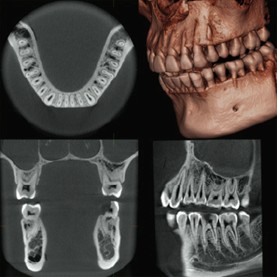

歯列全体を一目で確認できる『パノラマX線撮影』

お口全体の健康チェックを

パノラマX線撮影は、上下の歯列・顎の骨・顎関節を一度に撮影できる検査です。お口全体の健康状態を把握し、異常を早期発見するのに役立ちます。

こんな診断に活用されます

- 虫歯・歯周病の進行確認

- 歯根や骨の状態チェック(根尖病変・骨吸収の有無など)

- 親知らずの位置や生え方の診断

- 顎関節や顎の骨の異常発見

- 初診時の総合診断・定期検診での経過観察

目に見えない病変を早期発見できるため、症状が出る前の予防ケアにもつながります。

お口の状態は日々変化するため、年1回のパノラマX線撮影を推奨しています。

定期的な検査で異常を早期発見し、適切な治療を受けましょう。

パノラマX線の特徴

- 高精細な画像で歯や顎の構造を鮮明に映し出す

- 成人・小児モードなど、多彩な撮影モードを搭載

- 短時間の撮影で負担が少なく、低被曝量